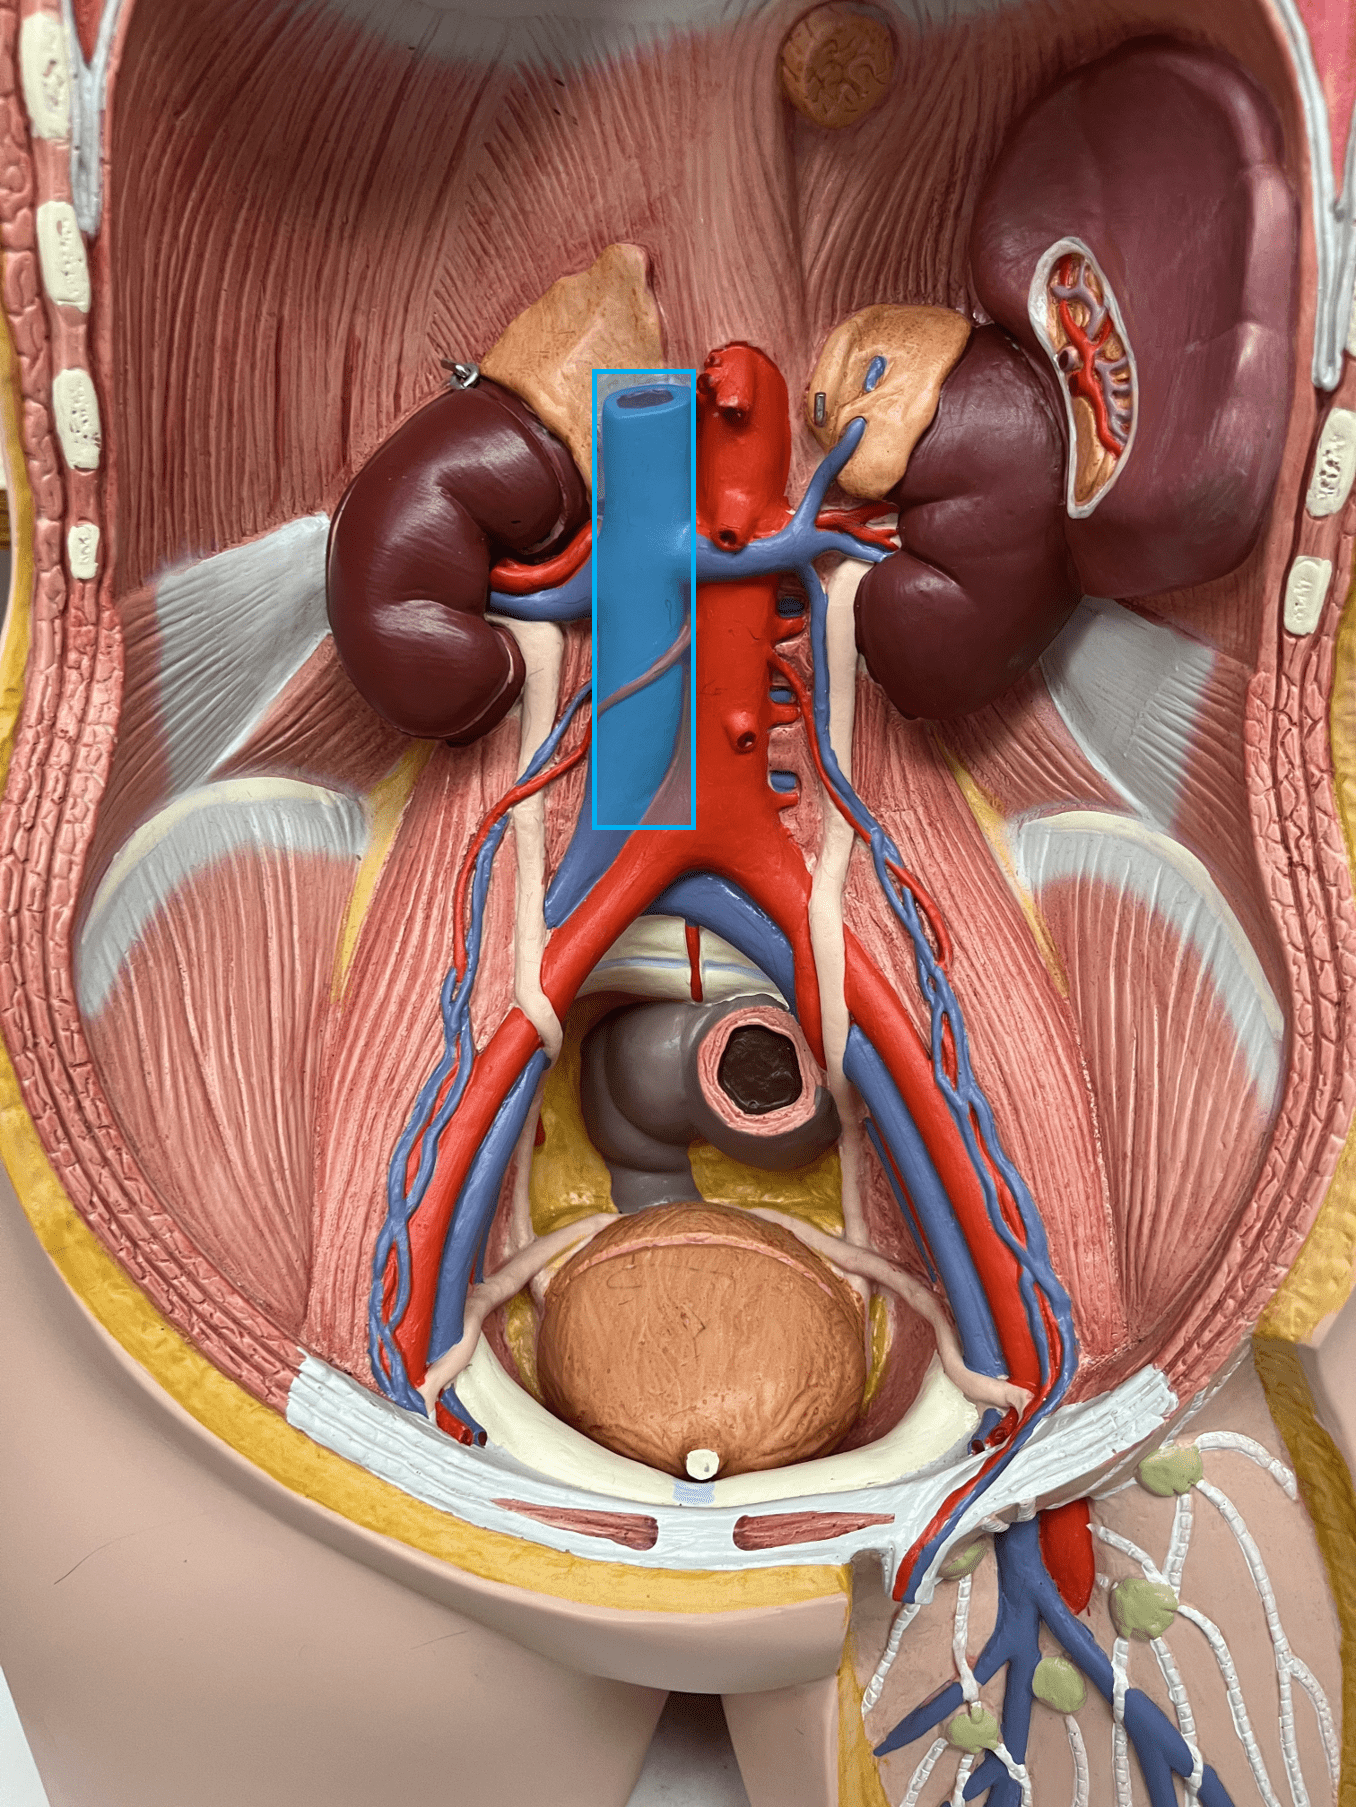

• The smooth muscle allows for vasoconstriction and vasodilation.